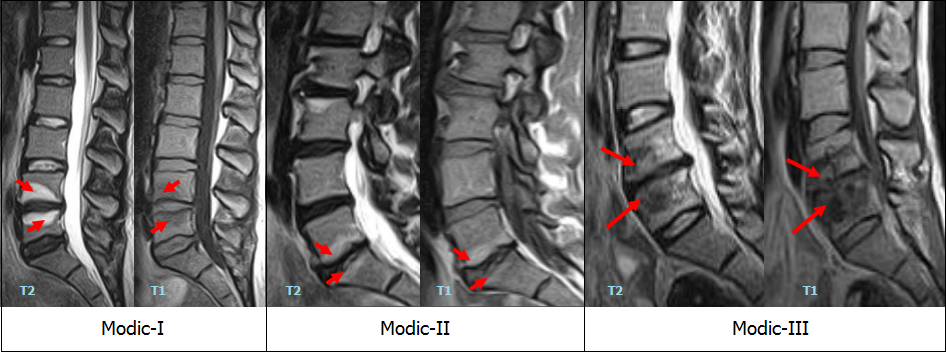

Мрт картина дегенеративно дистрофических изменений пояснично крестцового отдела позвоночника